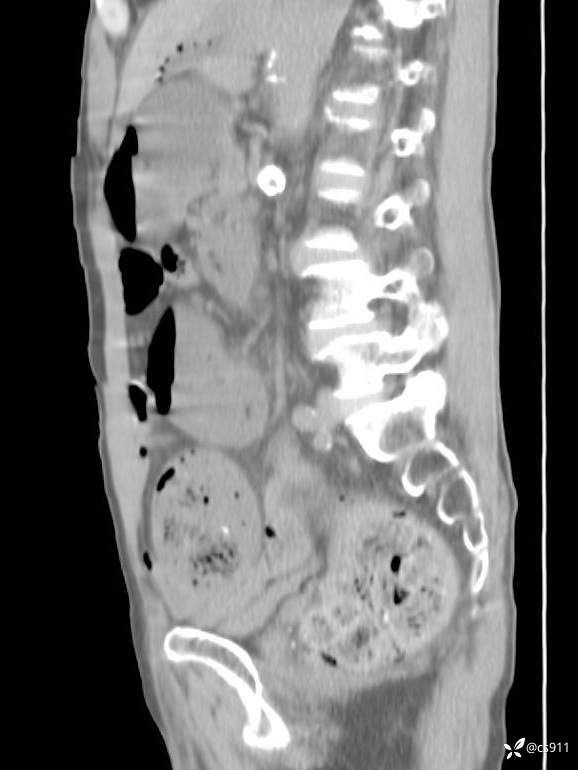

急腹症之急诊CT,原因?答案公布

男,77岁,腹痛、腹胀伴恶心呕吐1天。呕吐胃内容物,非喷射性呕吐,有咖啡色样胃内容物,诉有胃穿孔病史。查体:全腹平,下腹部压痛,全腹无反跳痛,叩诊呈浊音,移动性浊音阴性,肠鸣音减弱,1-2次/分。肛检:直肠未扪及明显肿物,可触及大量粪块。

T 36.6℃ P 80次/分 R 26次/分 BP 100/60mmHg

白细胞(WBC) H 14.55 10e9/L 4-10

中性粒细胞百分率(NEUT%) H 85.7 % 40-75

血淀粉酶(AMY) HH 1859 U/L 35-135

癌胚抗原(CEA) H 27.44 ng/ml 0-5

呕吐物 潜血试验 * 阳性 阴性

患者轮椅入室检查神志清楚, 能配合摆位和呼吸